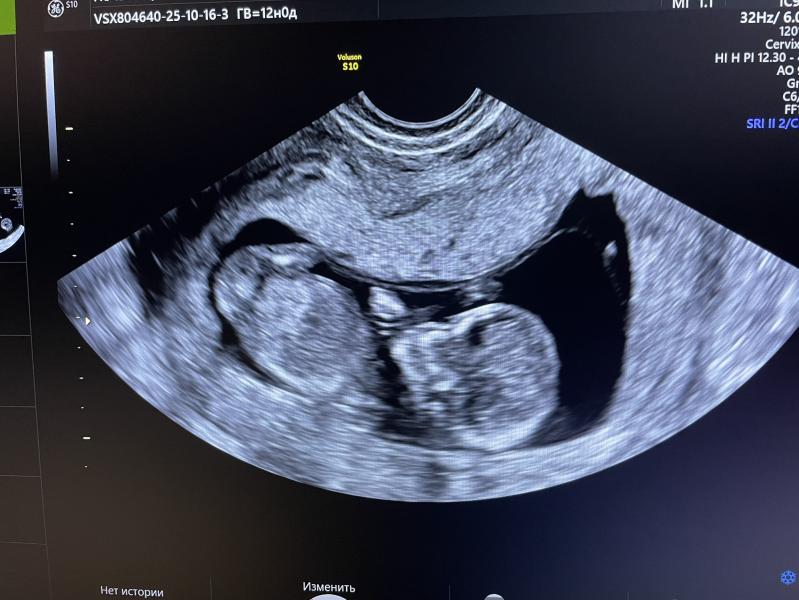

Первый скрининг пройден. По узи все хорошо, жду кровь, надеюсь на лучшее👌

Пупсик 5.9 см

По месячным 12 недель, по скринингу 12 недель и 2 дня, интересно как врач в итоге будет считать.